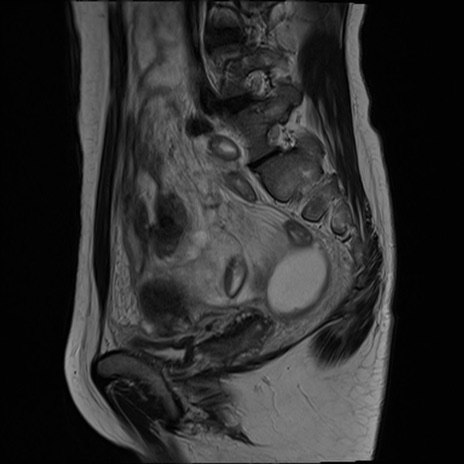

症例39 T2WI(矢状断像)

MRI(4日後)